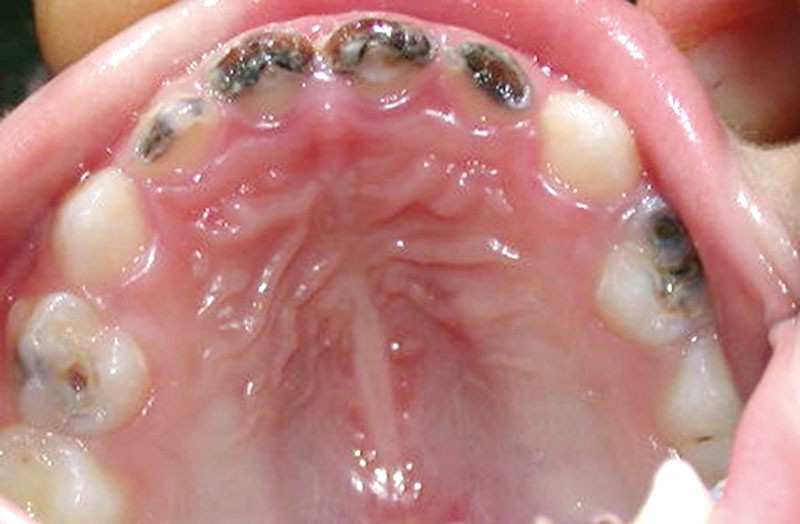

La carie précoce du jeune enfant est une forme sévère et particulièrement virulente de carie dentaire ; elle est définie par son caractère rampant, circulaire et sévère, l’âge de survenue situé entre 6 mois et 6 ans, et son étiologie plurifactorielle, notamment alimentaire (biberon sucré le soir ou au moment de la sieste, sirops pédiatriques…). Sa prise en charge par le pédodontiste est difficile, car l’enfant, à cet âge, n’est généralement pas coopérant pour recevoir les soins dentaires.

La carie précoce du jeune enfant se définit par la présence d’au moins une dent cariée (avec ou sans cavitation), absente ou obturée au niveau de la denture d’un enfant de 71 mois ou moins. On ajoute également la lettre S (sévère) : (S-CPE) dans certains cas, par exemple si l’enfant montre déjà des signes de caries sur au moins une surface lisse des dents avant l’âge de trois ans [1-4].

Un enfant (S.A.) de sexe masculin, âgé de 4 ans, est présenté en consultation au service de Pédodontie-Prévention à la faculté de médecine dentaire de Rabat (Maroc) pour une mise en état de sa cavité buccale. Il est accompagné par son père.

Pendant les deux premières années de sa vie, il a eu l’habitude néfaste, à l’origine de la forme sévère de polycaries observée, de s’endormir avec un biberon de lait sucré le soir. Ce comportement à risque a été associé au grignotage…